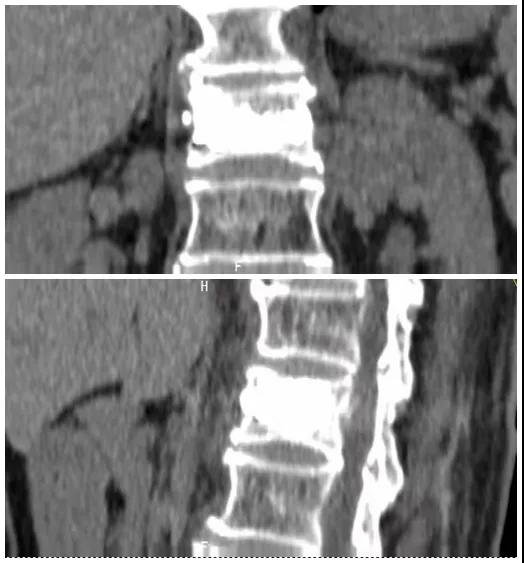

術(shù)前磁共振檢查提示腰1椎體新鮮壓縮性骨折

術(shù)后復(fù)查CT可見(jiàn)骨水泥彌散充分